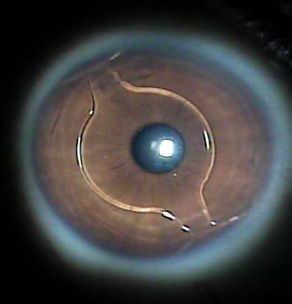

• Colocación de Lentes Fáquicos para Alta Miopía

(Acrysoft Fáquico Cachet) – Usado para la corrección de miopías moderadas a altas en pacientes que no son aptos para la cirugía de excimer láser. Consiste en la colocación de un lente plegable de material altamente compatible, de gran transparencia y calidad óptica específicamente desarrollado para uso intraocular. El procedimiento es una intervención rápida, en la cual el mismo día el paciente experimenta mejoría en su visión y a los pocos días se recupera totalmente sin depender de gafas o lentes de contacto

• Colocación de Anillos Intracorneales Fáquicos

En ciertos casos de alta miopía en los cuales la cirugía con Excimer Láser está contraindicada. Son segmentos de material sintético que no produce rechazo algunos; estos se colocan en el espesor de la córnea con el fin de producir estabilidad y aplanamiento en córneas muy curvas. Están indicados para detener la progresión del queratacono.